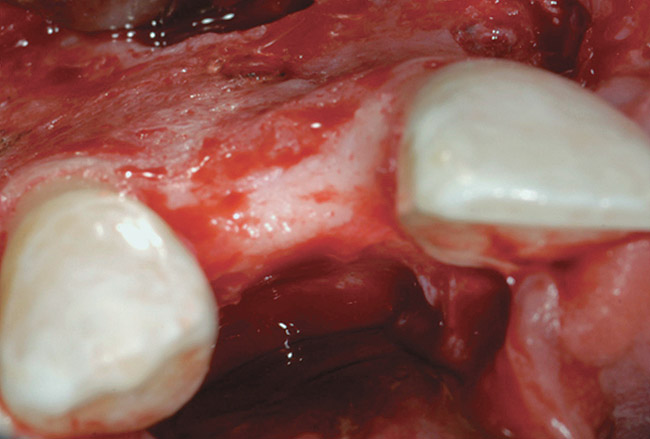

A 16-year-old female patient with a congenitally missing maxillary right lateral incisor was referred for an implant-supported crown. Clinical and CBCT evaluation revealed both a facial and palatal bony width deficiency (Figure 2 and Figure 3). The treatment plan included the use of titanium mesh and rhBMP-2/ACS (INFUSE® Bone Graft) along with mineralized allograft (MinerOss®, BioHorizons, www.BioHorizons.com) for bony augmentation (Figure 4 and Figure 5). After 7 months, the graft was found to be well incorporated and allowed for placement of a 3.8-mm x 10.5-mm diameter root form implant that was restored 3 months later (Figure 6, Figure 7, Figure 8, Figure 9 and Figure 10).

Figure 4  rhBMP-2/ACS plus mineralized allograft.

Figure 4

Figure 5  Titanium mesh/particulate graft complex.

Figure 5

Figure 6  Facial and palatal alveolar ridge width deficiency.

Figure 6